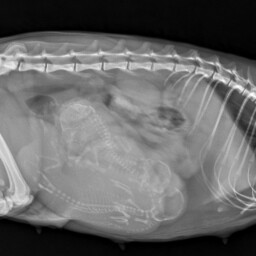

• Monitorowanie przebiegu ciąży (USG bardzo wysokiej jakości, RTG, badania hormonalne)

• Biometria płodowa (wyznaczanie terminu porodu na podstawie pomiarów struktur płodowych)